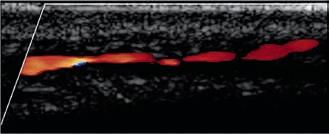

MR- und CT-Angiographie: In den letzten Jahren hat sich die nichtinvasive Bildgebung mittels MRA und CTA auch im Bereich der Darstellung der peripheren Arterien zu einer äußerst zuverlässigen Alternative zur DSA entwickelt. Die CTA und MRA sind beides hochpräzise Methoden, die eine genaue, detailgetreue Darstellung der arteriellen Anatomie, der artherosklerotischen Plaques und der Verengung des peripheren Gefäßsystems von der Aorta bis hinunter zu den Füßen ermöglichen (Abb. 6a, b). Mit beiden Verfahren lässt sich eine pAVK nicht nur zuverlässig darstellen, auch der Stenosegrad kann bestimmt werden. Beide Verfahren können zur Behandlung des gesamten Spektrums von Patienten mit

Abb. 6a

Abb. 6b

Abbildung 6a, b: Darstellung peripherer Arterien.

a: Die MR-Angiographie der distalen Aorta bis zum Femoralbereich zeigt einen Verschluss der A. femoralis superficialis (AFS) links sowie einen iliakalen Stent links.

b: CT-Angiographie der Bifurkation der Aorta abdominalis.

vermuteter oder bekannter pAVK eingesetzt werden. Hinsichtlich der diagnostischen Genauigkeit und dem Nachweis sowie der Einstufung einer peripheren Arterienerkrankung ähneln sich die MRA und CTA in Sensitivität und Spezifität, die bei beiden 90 – 100 % betragen. Die am häufigsten verwendete

MRA-Methode ist aktuell die kontrastmittelverstärkte MRA, aber auch das nicht kontrastmittelverstärkte Verfahren wird zunehmend eingesetzt, da hierbei kein Kontrastmittel appliziert werden muss.